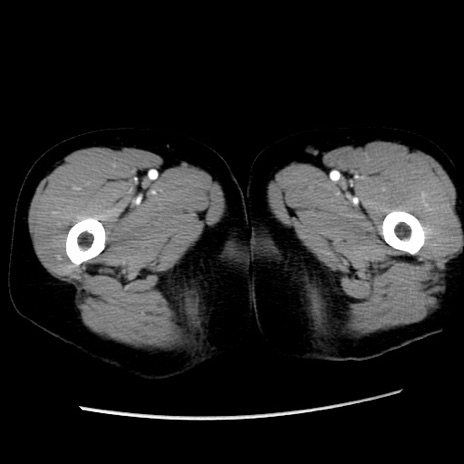

冠状断像